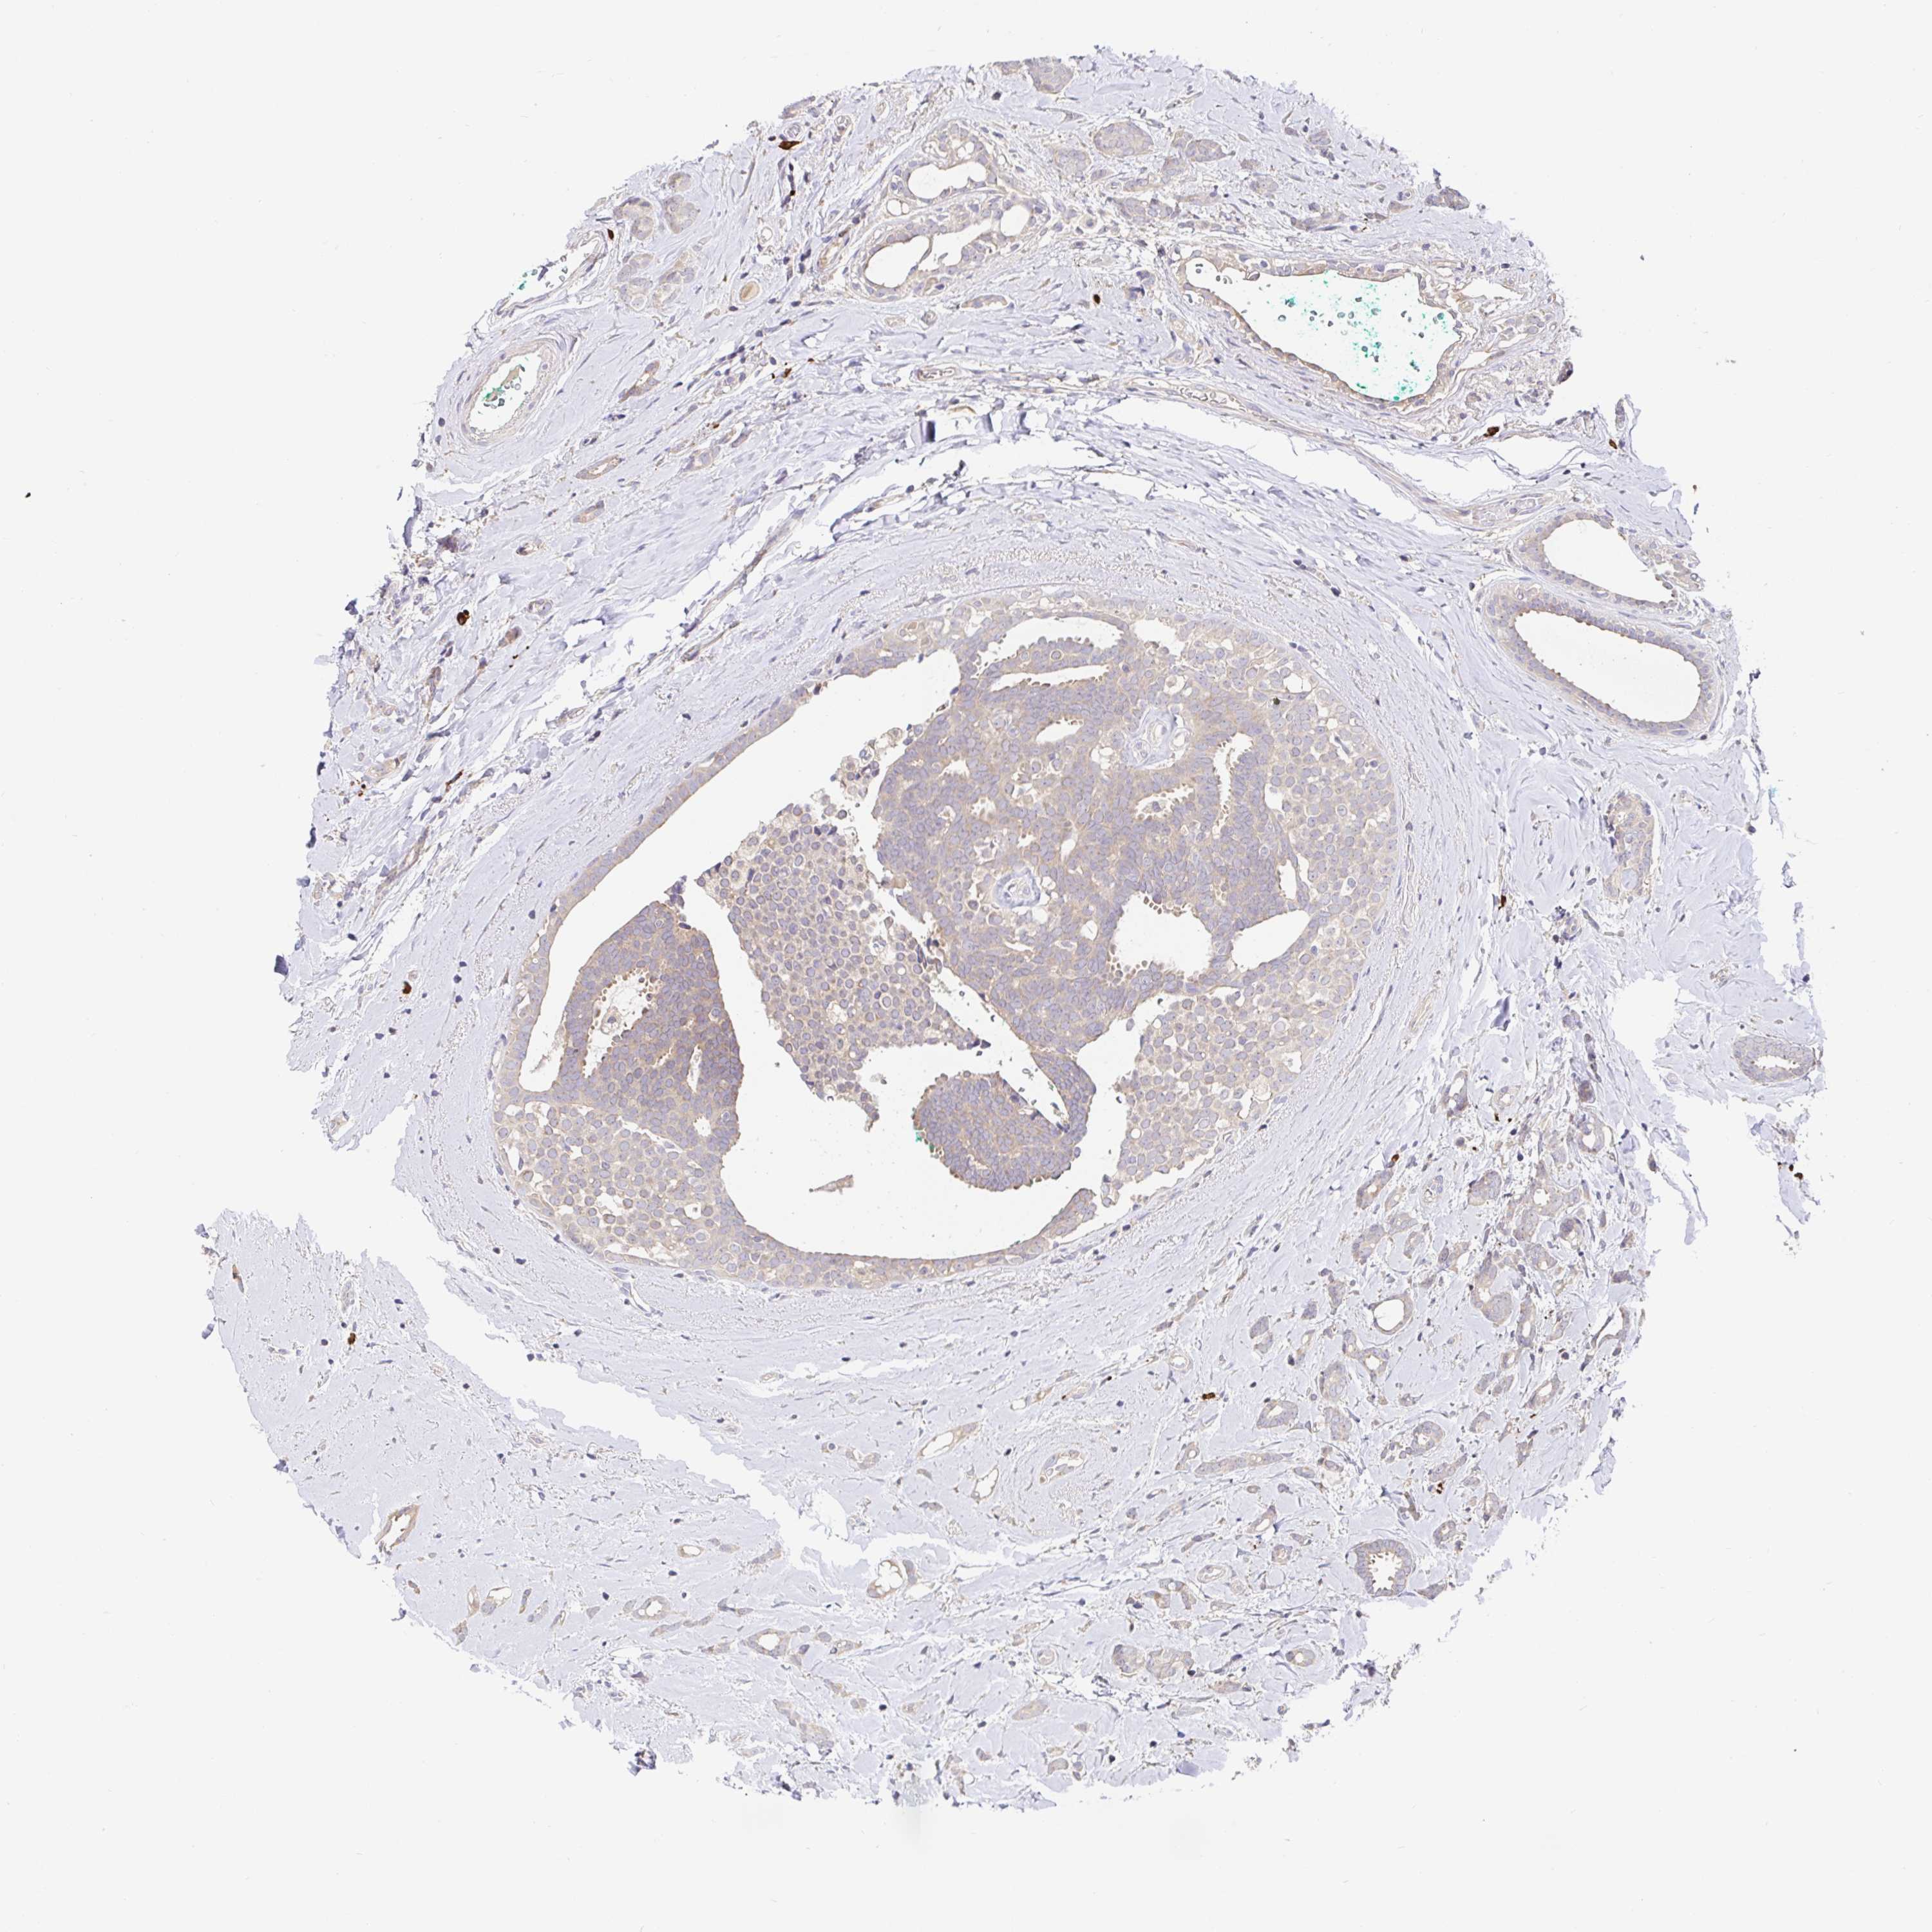

CANCER BREAST CANCER Show tissue menu

BRCA TCGA BRCA VALIDATION PROTEIN EXPRESSION